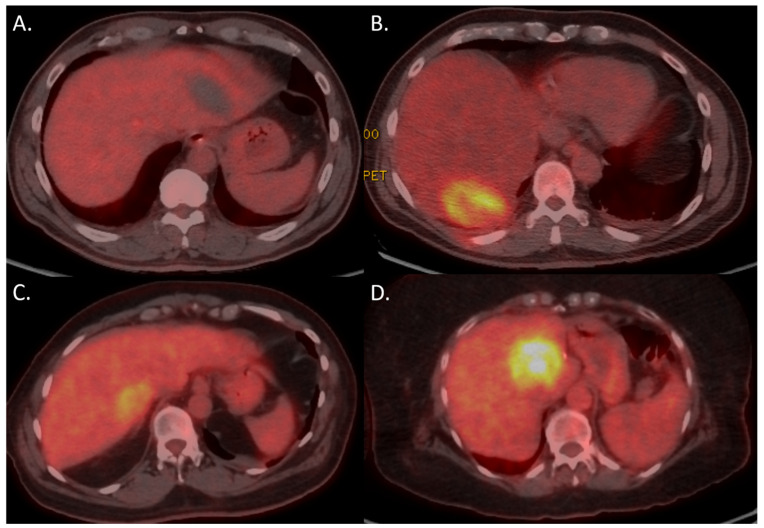

目的是确定18-氟脱氧葡萄糖(18F-FDG)正电子发射断层扫描-计算机断层扫描(PET-CT)在经皮图像引导的原发性和转移性恶性肿瘤消融后24小时内进行扫描的能力,以预测消融效果和局部肿瘤进展(LTP)。这项单中心回顾性研究纳入了2018年8月至2024年2月期间接受图像引导消融(微波消融(MWA)、冷冻消融或不可逆电穿孔(IRE))治疗原发性和转移性恶性肿瘤的患者。主要结局指标包括消融后18F-FDG PET-CT结果与每个肿瘤LTP发展的相关性,使用卡方检验进行评估。次要结局指标是每个肿瘤的局部肿瘤无进展生存期(LTPFS),使用Kaplan-Meier生存曲线进行评估,并利用Cox比例风险回归模型进行多变量分析,确定潜在的混杂因素。共包括132名患者,他们接受了159次手术,治疗了224个肿瘤。在随访期间,224例肿瘤中有120例(53.6%)发生LTP。消融后24 h内PET-CT上残留结节性18F-FDG的存在与随访影像LTP的发生有显著相关性(p < 0.001)。结节性18F-FDG的阳性预测值为86.7%。在多变量分析中,18F-FDG贪婪的危险比(HR)为2.355 (95% CI 1.614-2.647; p < 0.001)。消融后24 h内PET-CT上18F-FDG的存在与LTP的发生及LTPFS的降低高度相关。残留肿瘤组织的检测可能允许早期再治疗,特别是在结节性摄取的肿瘤中,这有助于增加LTPFS。

The purpose was to determine the ability of 18-fluorodeoxyglucose (18F-FDG) positron emission tomography-computed tomography (PET-CT) scans performed within 24 h of percutaneous image-guided ablation of primary and metastatic malignancies to predict ablation effectiveness and local tumor progression (LTP). This single-center retrospective review included patients who underwent image guided ablation (microwave ablation (MWA), cryoablation, or irreversible electroporation (IRE)) between August 2018 and February 2024 for primary and metastatic malignancies. The primary outcome measure encompassed correlating post-ablation 18F-FDG PET-CT findings with LTP development per tumor, assessed using the chi-square test. The secondary outcome measure was local tumor progression-free survival (LTPFS) per tumor, evaluated using the Kaplan-Meier survival curves, and potential confounders were identified in multivariable analysis utilizing Cox proportional hazards regression models. A total of 132 patients, who underwent 159 procedures for 224 tumors, were included. During follow-up, LTP developed in 120 out of 224 tumors (53.6%). The presence of residual nodular 18F-FDG avidity on PET-CT within 24 h after the ablation significantly correlated with the development of LTP at follow-up imaging (p < 0.001). The positive predictive value of nodular 18F-FDG avidity was 86.7%. In multivariable analysis, the hazard ratio (HR) for 18F-FDG avidity was 2.355 (95% CI 1.614-2.647; p < 0.001). The presence of 18F-FDG avidity on PET-CT within 24 h after the ablation was highly correlated with development of LTP and decreased LTPFS. The detection of residual tumor tissue may allow early re-treatments, especially in tumors with nodular uptake, contributing to increased LTPFS.